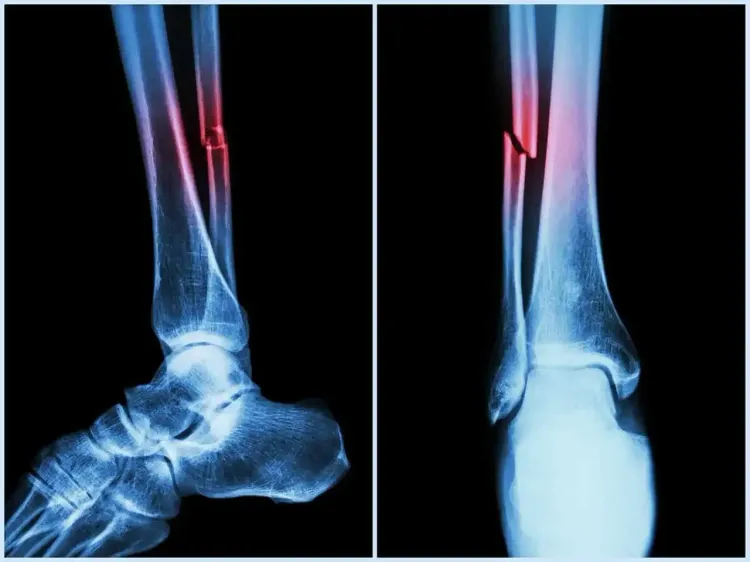

New Delhi, Aug 13 (NationPress) Researchers at the National Institute of Technology (NIT) Rourkela have discovered how natural sugar-like molecules within the human body can modify the behavior of a protein vital for bone formation and repair.

The study, featured in the journal Biochemistry, holds potential for advanced therapies in bone and cartilage regeneration, enhanced implants, and more effective protein-based treatments.

In this context, Bone Morphogenetic Protein-2 (BMP-2) is crucial for the formation of bones and cartilage, injury healing, and directing stem cells to differentiate into bone-forming cells, as noted by the NIT research team.